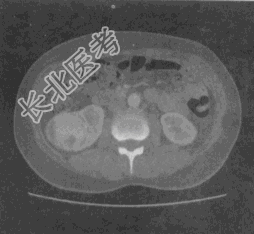

- 单项选择题患者,女, 52岁。无痛性血尿4天。双侧肾区CT平扫加增强扫描如图所示。最有可能的诊断是

A、肾囊肿

B、肾结核

C、肾错构瘤

D、肾盂癌

E、肾癌